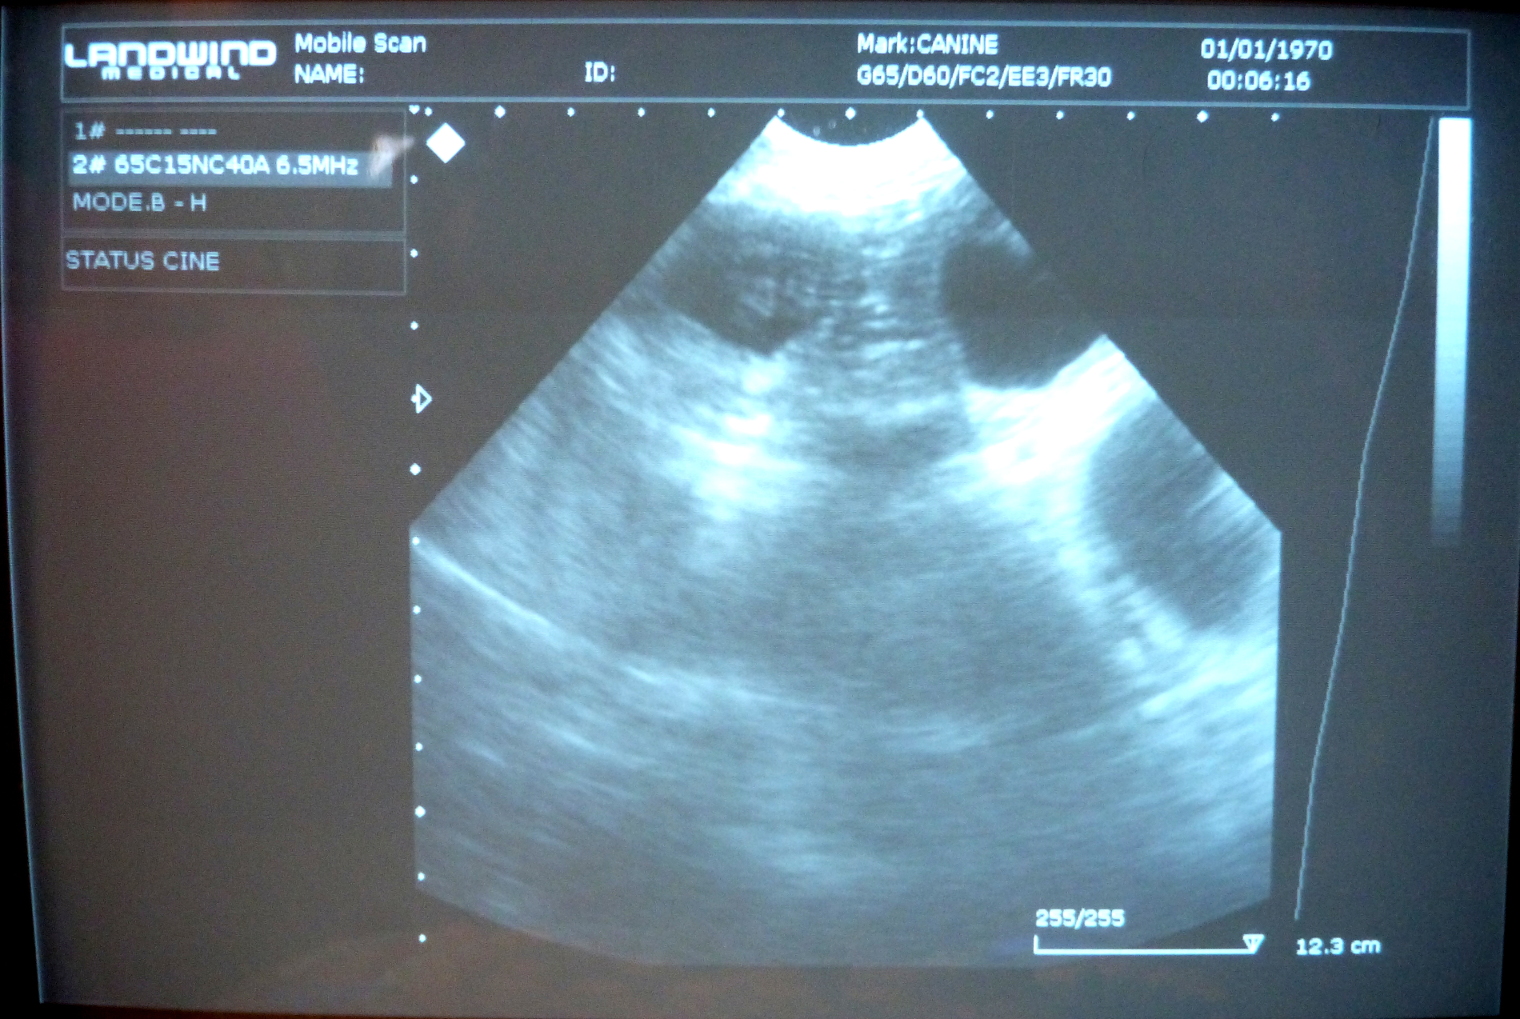

Forthcoming Litter (Belatarr: the Next Generation) » Lyra Ultrasound Scan 6th March